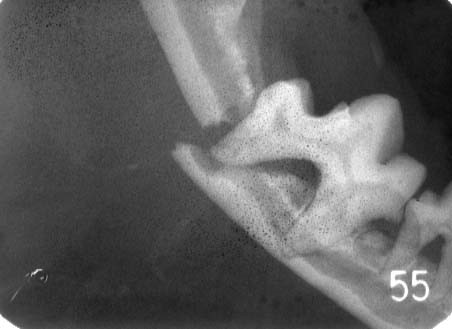

下顎骨骨折(かがくこつこっせつ)

小型犬の場合、下顎骨の厚さに比べて歯が相対的に大きいため、根尖(歯の根っこ)が下顎骨の下縁(下のライン)とほぼ同じような位置にあります。歯周病が進行し下顎骨が重度に溶けてしまうと、硬いものを咬んだり、外からの衝撃が加わったりしただけでも薄くなった下顎骨が簡単に折れてしまうことがあります。